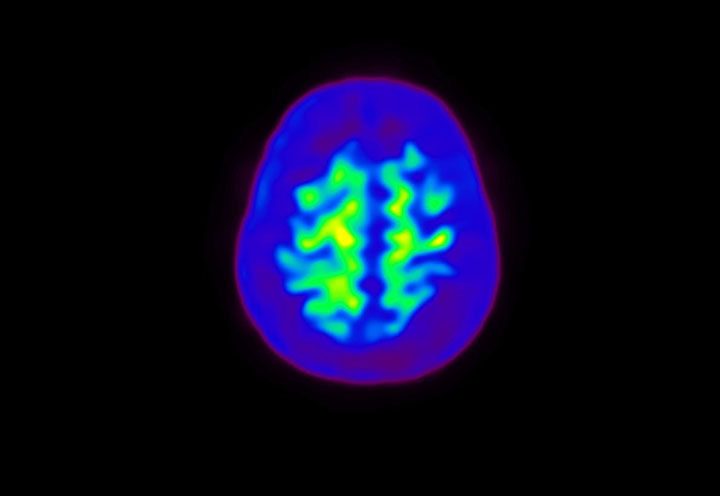

Head / Case4 : Amyloid

Coronal

Courtesy : Kindai University Hospital

- Imaging protocol

- Injected dose: 3.21 MBq/kg, 18F-Flutemetamol

- Uptake time: 100 minutes

- Scan time: 20 minutes